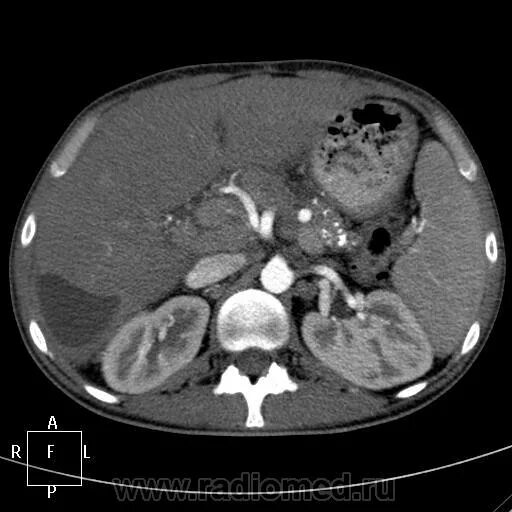

Плотность печени на кт